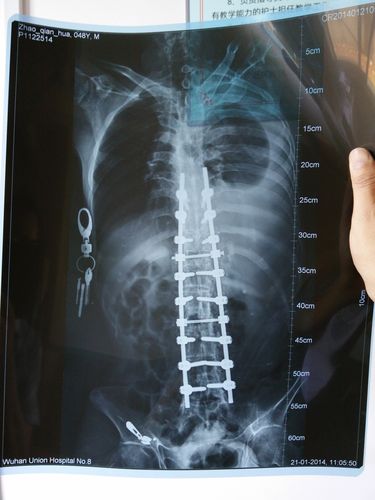

强直性脊柱炎可以导致残疾吗?

强直性脊柱炎是一种慢性病,在早期并没有明显的症状,患者也不会注意。随着病情的蔓延,逐渐的出现跛行等严重病症,加大了治疗的难度。所以及时治疗和预防相当重要,否则很容易导致残疾,或带来其他的并发症。(参考:常州解放军102医院骨科)

? 虽然强直性脊柱炎是一种慢性、进行性、致残性的风湿病,但是恰当的治疗、生活习惯的调整和适宜的锻炼,完全可以阻止或延缓疾病发展至残废。

强直性脊柱炎是一种致残性的疾病。因此,其治疗不但要止痛,更重要的是控制病情,改善和恢复脊柱关节的功能,阻止病情发展至关节功能障碍,防止步入残废。